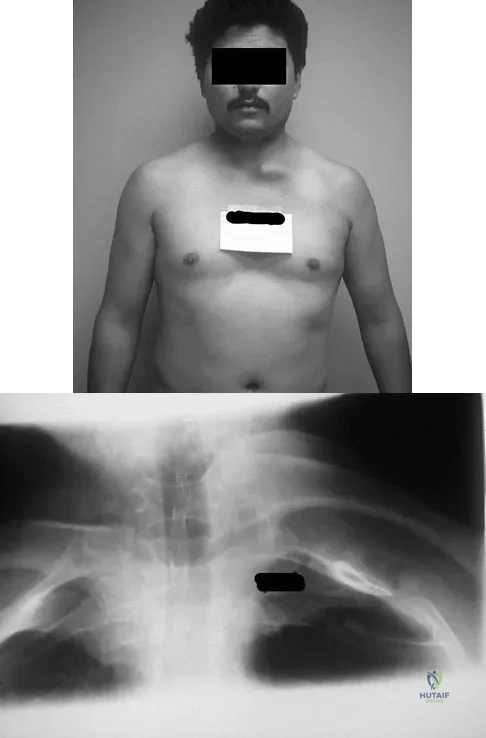

Question 8High Yield

A 66-year-old man has a high-grade angiosarcoma of the right tibia. A radiograph is shown in Figure 43. Treatment should consist of

Explanation